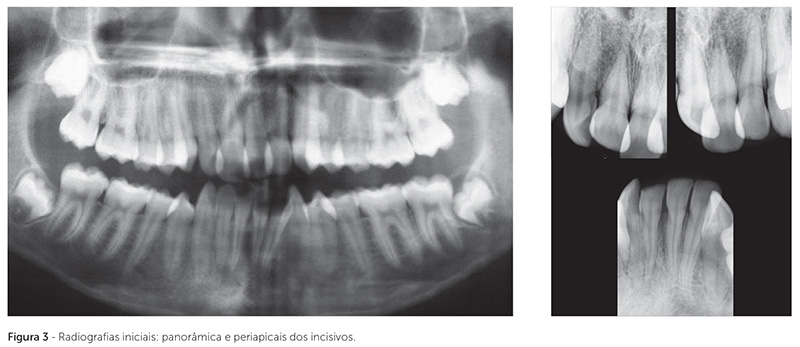

Nas radiografias panorâmica e periapicais dos incisivos (Fig. 3), foi possível observar boa formação radicular de todos os dentes, ausência de rarefação apical no dente 41 fraturado e ausência de anomalias ósseas ou dentárias. Os terceiros molares estavam inclusos e no estágio 6 de Nolla, estando em fase inicial de formação radicular.